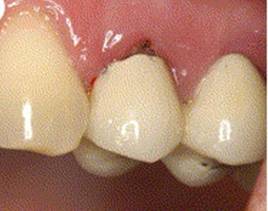

PROSTHESIS

OSTEOINTEGRATE DENTAL IMPLANT SURGERY